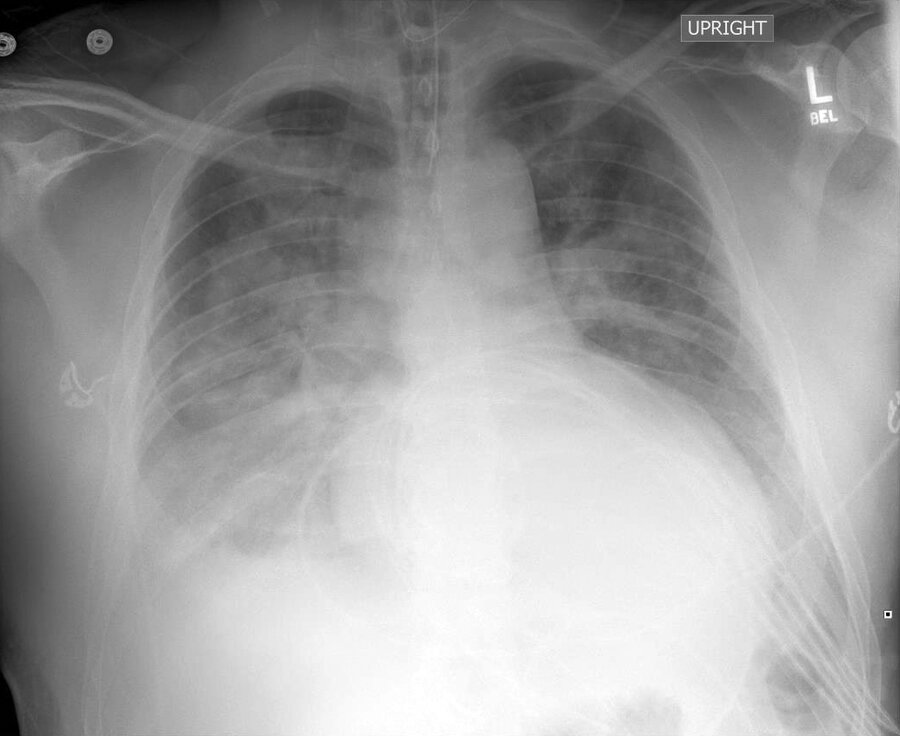

A 59-year-old man is hospitalized with acute hypoxemic respiratory failure requiring intubation.

A frontal chest radiograph is shown.

Which of the following is the most likely diagnosis?

This frontal chest radiograph reveals bilateral alveolar opacifications with air bronchograms, consistent with multilobar pneumonia (option C).

The right and left hemidiaphragms are each partially obscured, with placement of infiltrates in the right and left lower lobes, respectively. The right heart border is partially obscured, and an infiltrate within the right middle lobe is also possible.